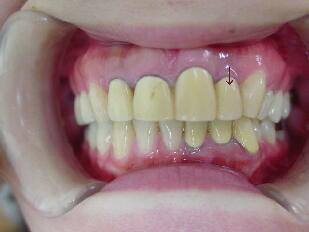

C、部分矯正の後、セラミック冠で治療した症例(上下6本前歯部)

左上側切歯(↓)が口蓋側(内面方向)に強く傾斜して、術前では根面板(根に金属の蓋がし

てある状態)で、上の前歯部はブリッジの状態でした。その歯を唇側に引き出して1歯ずつ 独立した状態にし、セラミック冠を装着しました。歯磨きが容易になったので歯肉状態が 改善され、きれいなピンク色を呈しています。 4.低位咬合の改善